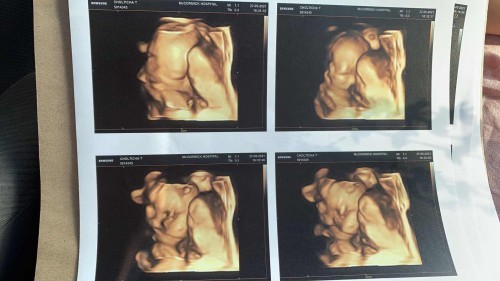

เรารู้เพศก็ทยอยซื้อแล้วค่ะ กลัวท้องใหญ่กว่านี้แล้วไปไม่ได้ ตอนนี้ 7 เดือน เริ่มเมื่อยง่าย เหนื่อยง่ายแล้วค่ะ วันนี้ซาวด์ชัดเจนแจ่มแจ้ง ผู้หญิง 100%